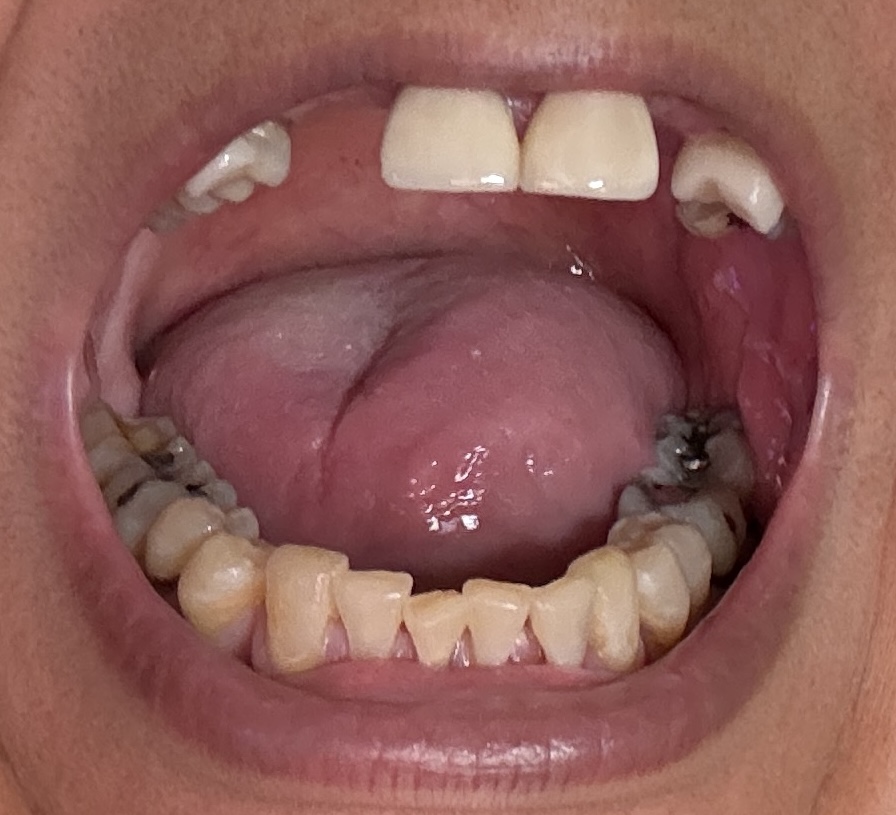

12,13,14 have had root canals in past and now have quite a bit movement. 2-5 have all had root canals in past and now the crowns are breaking down.

Overall information (lower arch)

Overall, all of my gums have receded and most of the bottom teeth are exposed w/ some roots and there are many cavities.